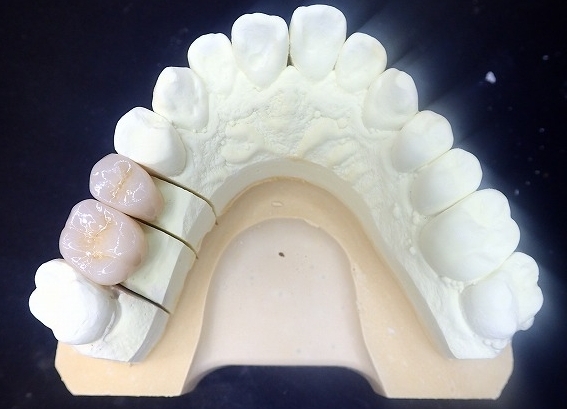

最初は上顎左側のジルコニアクラウン製作

すでにファイバーコアの装着が終わっています。

左上 ジルコニアクラウン装着

ジルコニアを制作する前に

上記のようなリスクがあるので、

それを理解の上での意思決定により

制作開始となります。

左右5本をジルコニアクラウンにすることができました。

上顎の歯がすべて揃いました。